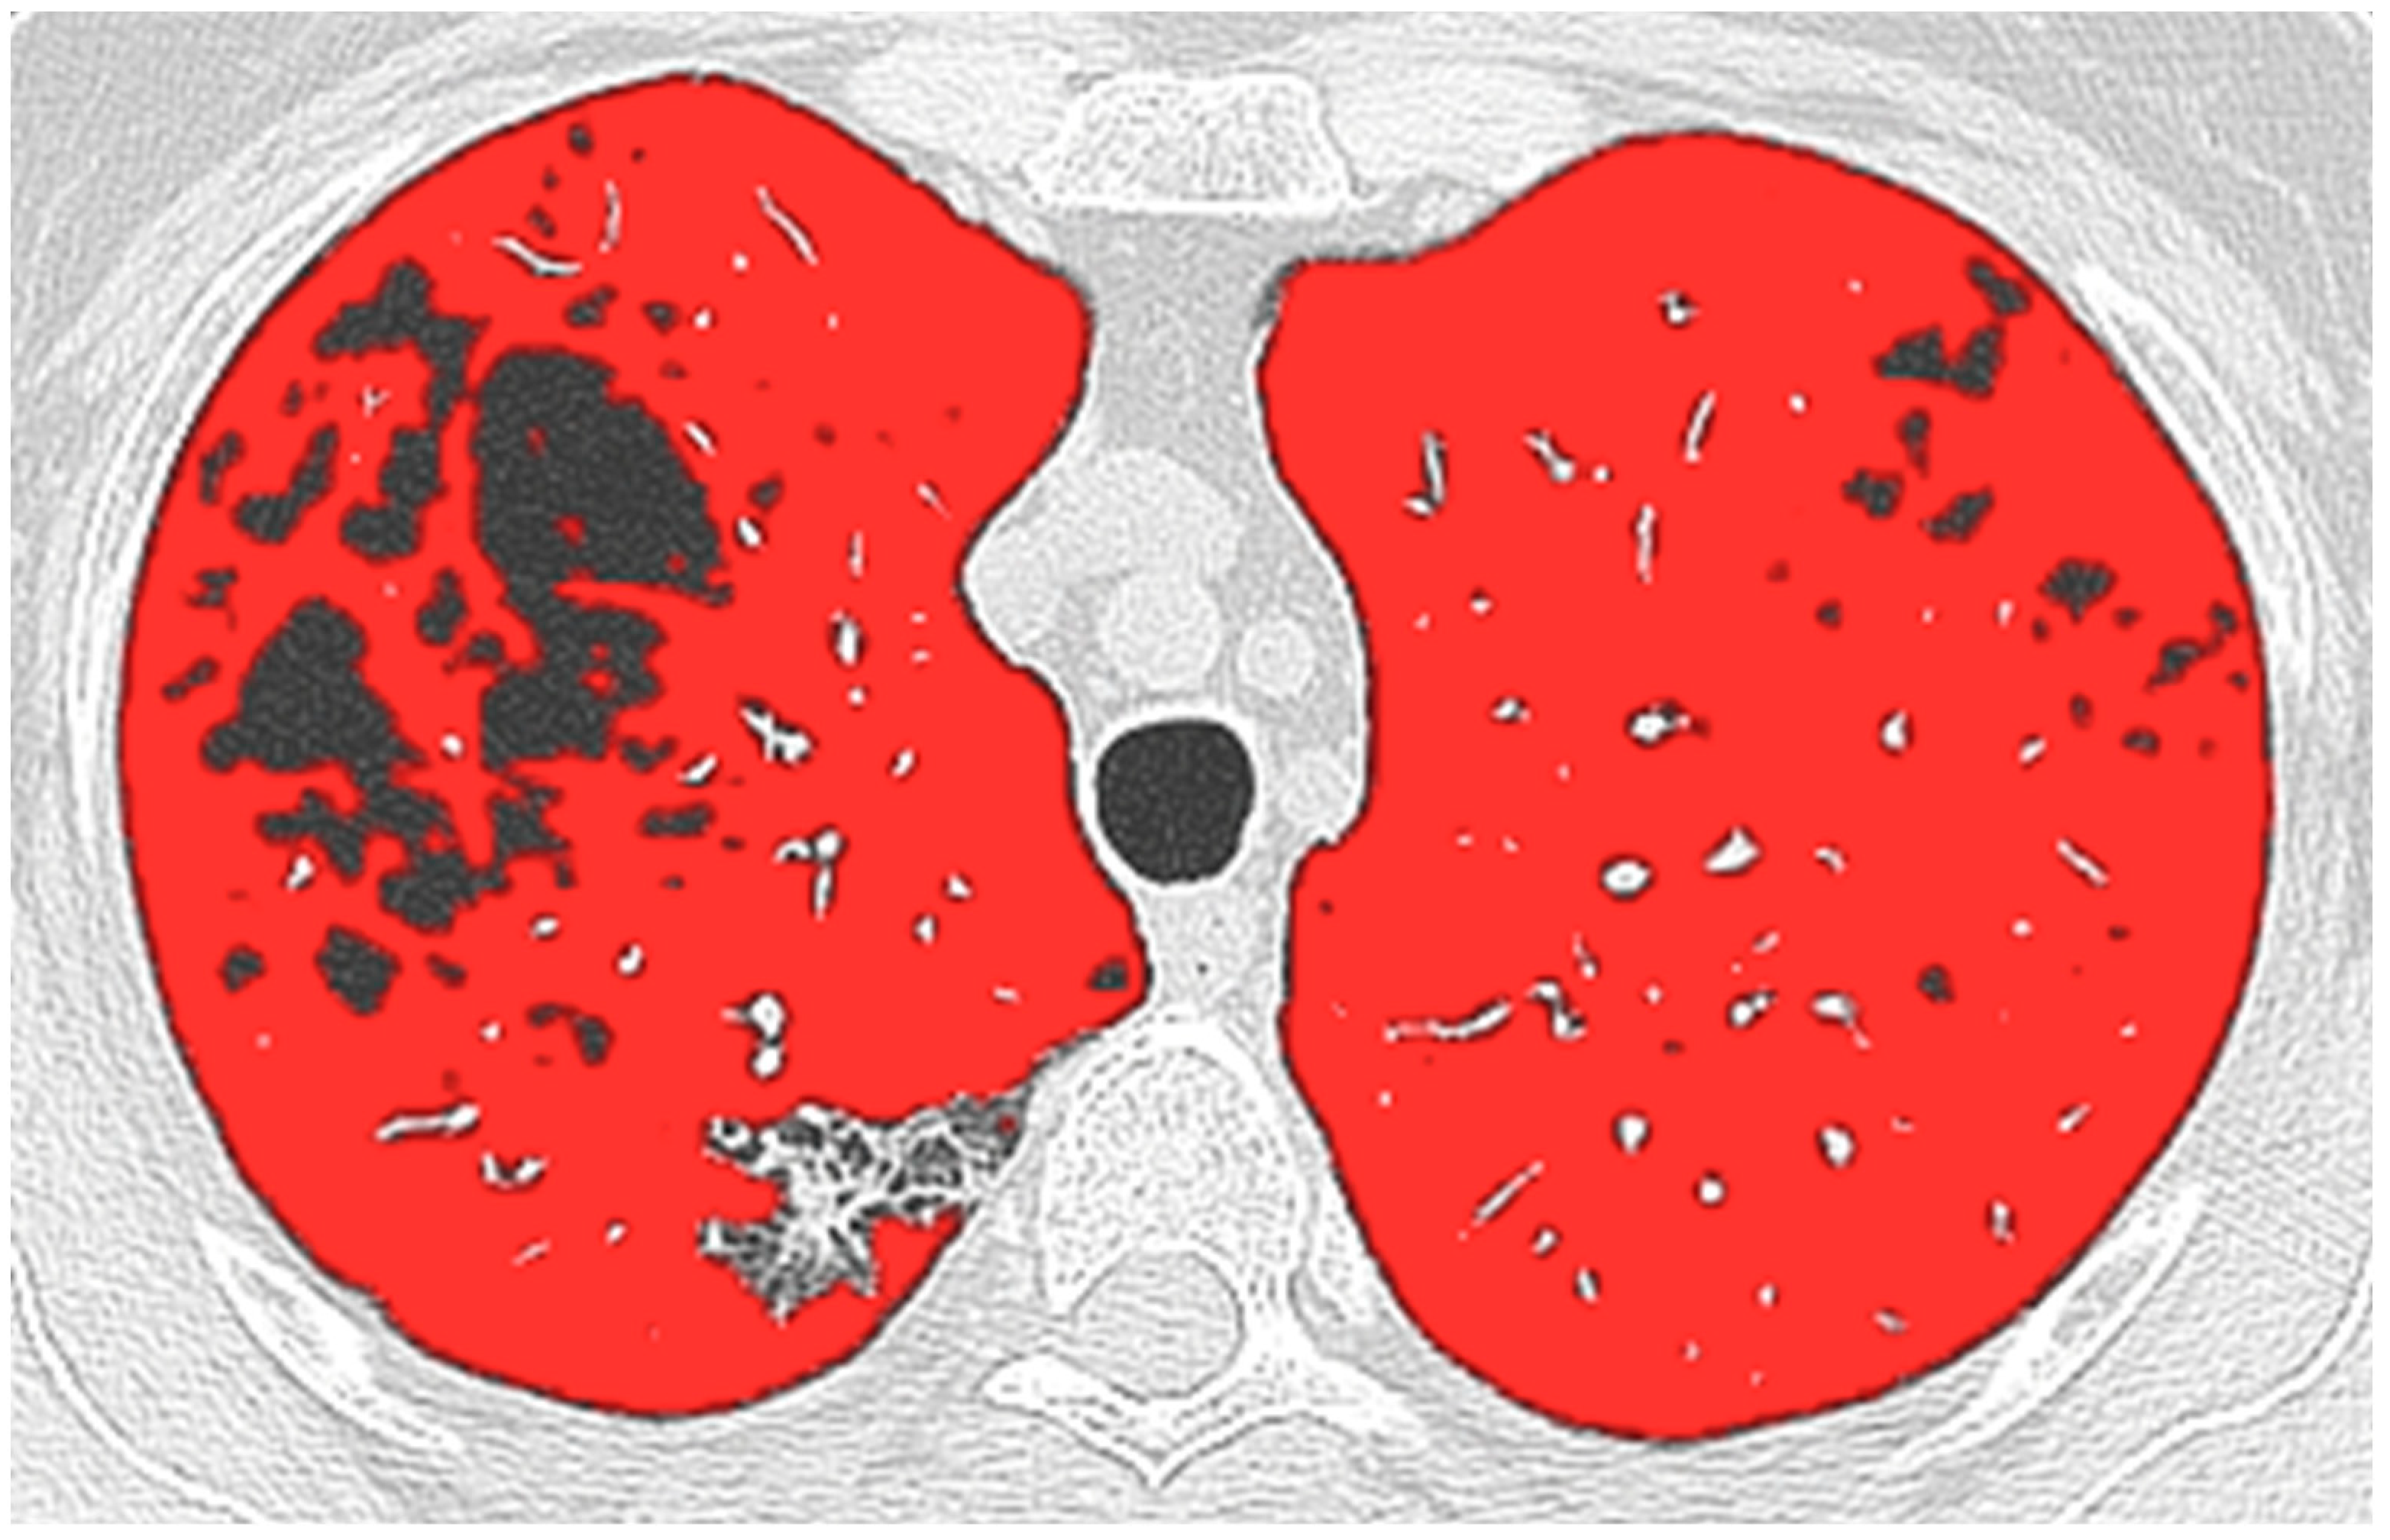

2.3. CT and Computer Analysis

- Risoli, C.; Nicol, M.; Colombi, D.; Moia, M.; Rapacioli, F.; Anselmi, P.; Michieletti, E.; Ambrosini, R.; Di Terlizzi, M.; Grazioli, L.; et al. Different Lung Parenchyma Quantification Using Dissimilar Segmentation Software: A Multi-Center Study for COVID-19 Patients. Diagnostics 2022, 92, 1501. [Google Scholar] [CrossRef]

- Colombi, D.; Bodini, F.C.; Petrini, M.; Maffi, G.; Morelli, N.; Milanese, G.; Silva, M.; Sverzellati, N.; Michieletti, E. Well-Aerated Lung on Admitting Chest CT to Predict Adverse Outcome in COVID-19 Pneumonia. Radiology 2020, 296, 201433. [Google Scholar] [CrossRef] [PubMed]